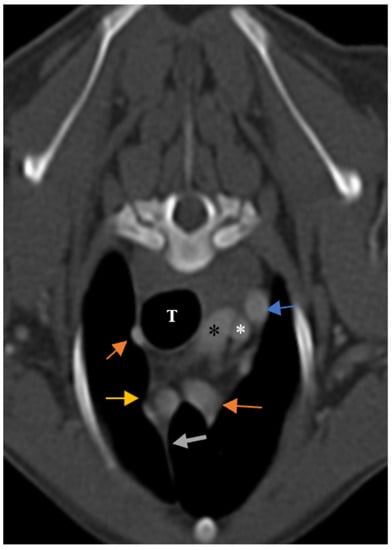

Figure 5. Demonstration of visibility and topographic location of grade 2 thymus in contrast-enhanced transverse sections of the thoracic region at the level of T3 in both patients. (A): One-year-old female mixed-breed dog with a visible, grade 2, wedge-shaped thymus with midline predominancy, mottled appearance and concave border (CT number: 75). (B): Two-year-old female mixed-breed dog with a visible, grade 2, wedge-shaped thymus with left-sided predominancy, mottled appearance and concave border (CT number: 79). Light grey dash lines illustrate thymic borders. CrVC: cranial vena cava, E: esophagus (which is dilated due to general anesthesia), blue arrow: left subclavian artery, green arrow: brachiocephalic trunk, blue arrowheads: internal thoracic arteries, yellow arrow: right common carotid artery, orange arrow: left common carotid artery, and asterisk: right subclavian artery.